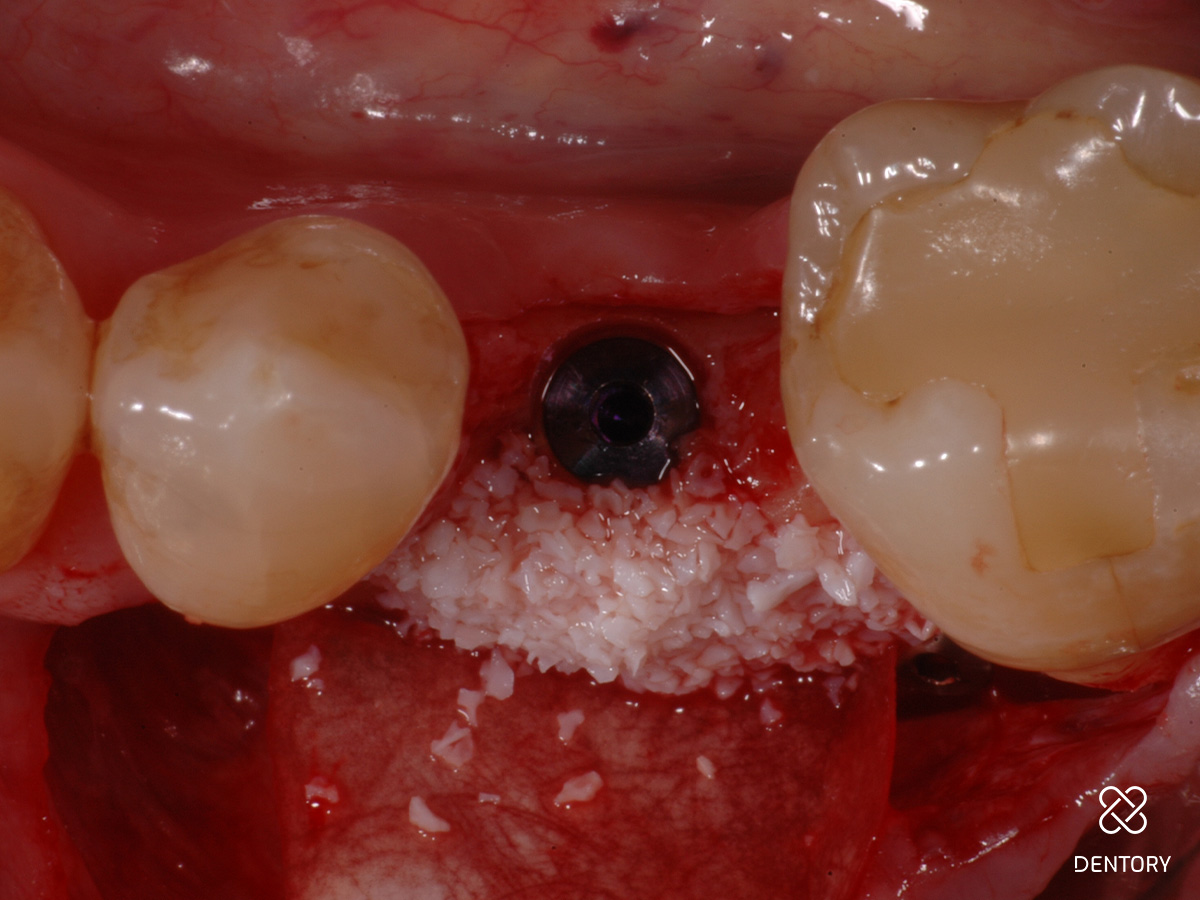

Abbildung 3

Okklusale Ansicht nach Insertion eines 4 mm-Implantats mit Plattform-Switching. Eine simultane Defektrekonstruktion erscheint möglich.